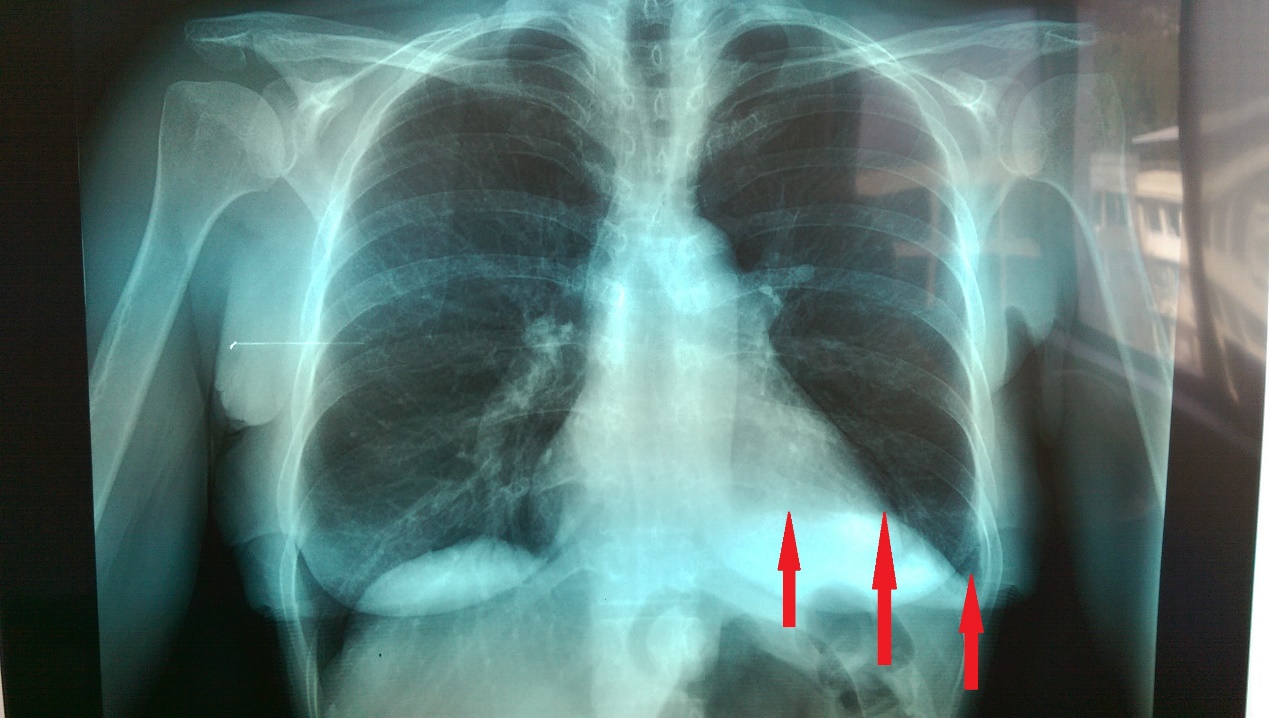

Ακτινογραφία θώρακος μετά από πλύχυνση του αριστερού διαφράγματος. Η πλήρης έκπτυξη του αριστερού πνεύμονα είναι εμφανής. Το αριστερό διάφραγμα πλέον φαίνεται ισιωμένο σε φυσιολογική θέση (Ευγενική παραχώρηση Dr. V. Penopoulos)